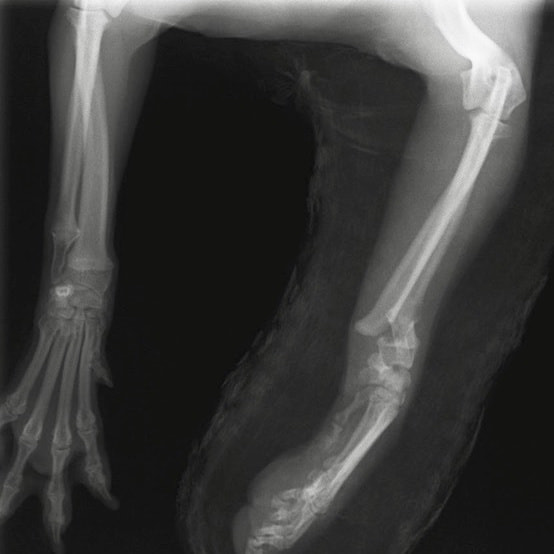

症例3:キルシュナーワイヤーのピンニングによる整復

ペルシャ猫 11ヶ月齢 雄

他院にて左大腿骨遠位の成長板骨折(salter-harrisⅠ型)が認められており、治療相談を目的として来院。当院にて、キルシュナーワイヤーを用いたピンニングにより骨折部位の整復を行いました。術後の経過は良好で、現在も経過観察中です。

術前レントゲン

術後レントゲン